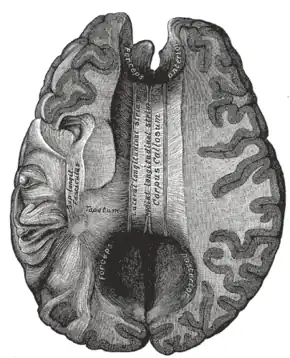

Corpus callosum from above, front part at the top of the image.

The corpus callosum has four main parts – individual nerve tracts that connect different parts of the hemispheres. These are the rostrum, the genu, the trunk or body, and the splenium.[4] A narrowed part between the trunk and the splenium is known as the isthmus. Fibres from the trunk and the splenium known together as the tapetum form the roof of each lateral ventricle.[6]

The front part of the corpus callosum, towards the frontal lobes, is called the genu ("knee"). The genu curves downward and backward in front of the septum pellucidum, diminishing greatly in thickness. The lower, much thinner part is the rostrum and is connected below with the lamina terminalis, which stretches from the interventricular foramina to the recess at the base of the optic stalk. The rostrum is named for its resemblance to a bird's beak.

The end part of the corpus callosum, towards the cerebellum, is called the splenium. This is the thickest part, and overlaps the tela choroidea of the third ventricle and the midbrain, and ends in a thick, convex, free border. Splenium translates as "bandage" in Greek.

The trunk of the corpus callosum lies between the splenium and the genu.

On either side of the corpus callosum, the fibers radiate in the white matter and pass to the various parts of the cerebral cortex; those curving forward from the genu into the frontal lobes constitute the forceps minor (also forceps anterior) and those curving backward from the splenium into the occipital lobes, the forceps major (also forceps posterior).[4] Between these two parts is the main body of the fibers, which constitute the tapetum and extend laterally on either side into the temporal lobe, and cover in the central part of the lateral ventricle. The tapetum and anterior commissure share the function of connecting left and right temporal lobes.